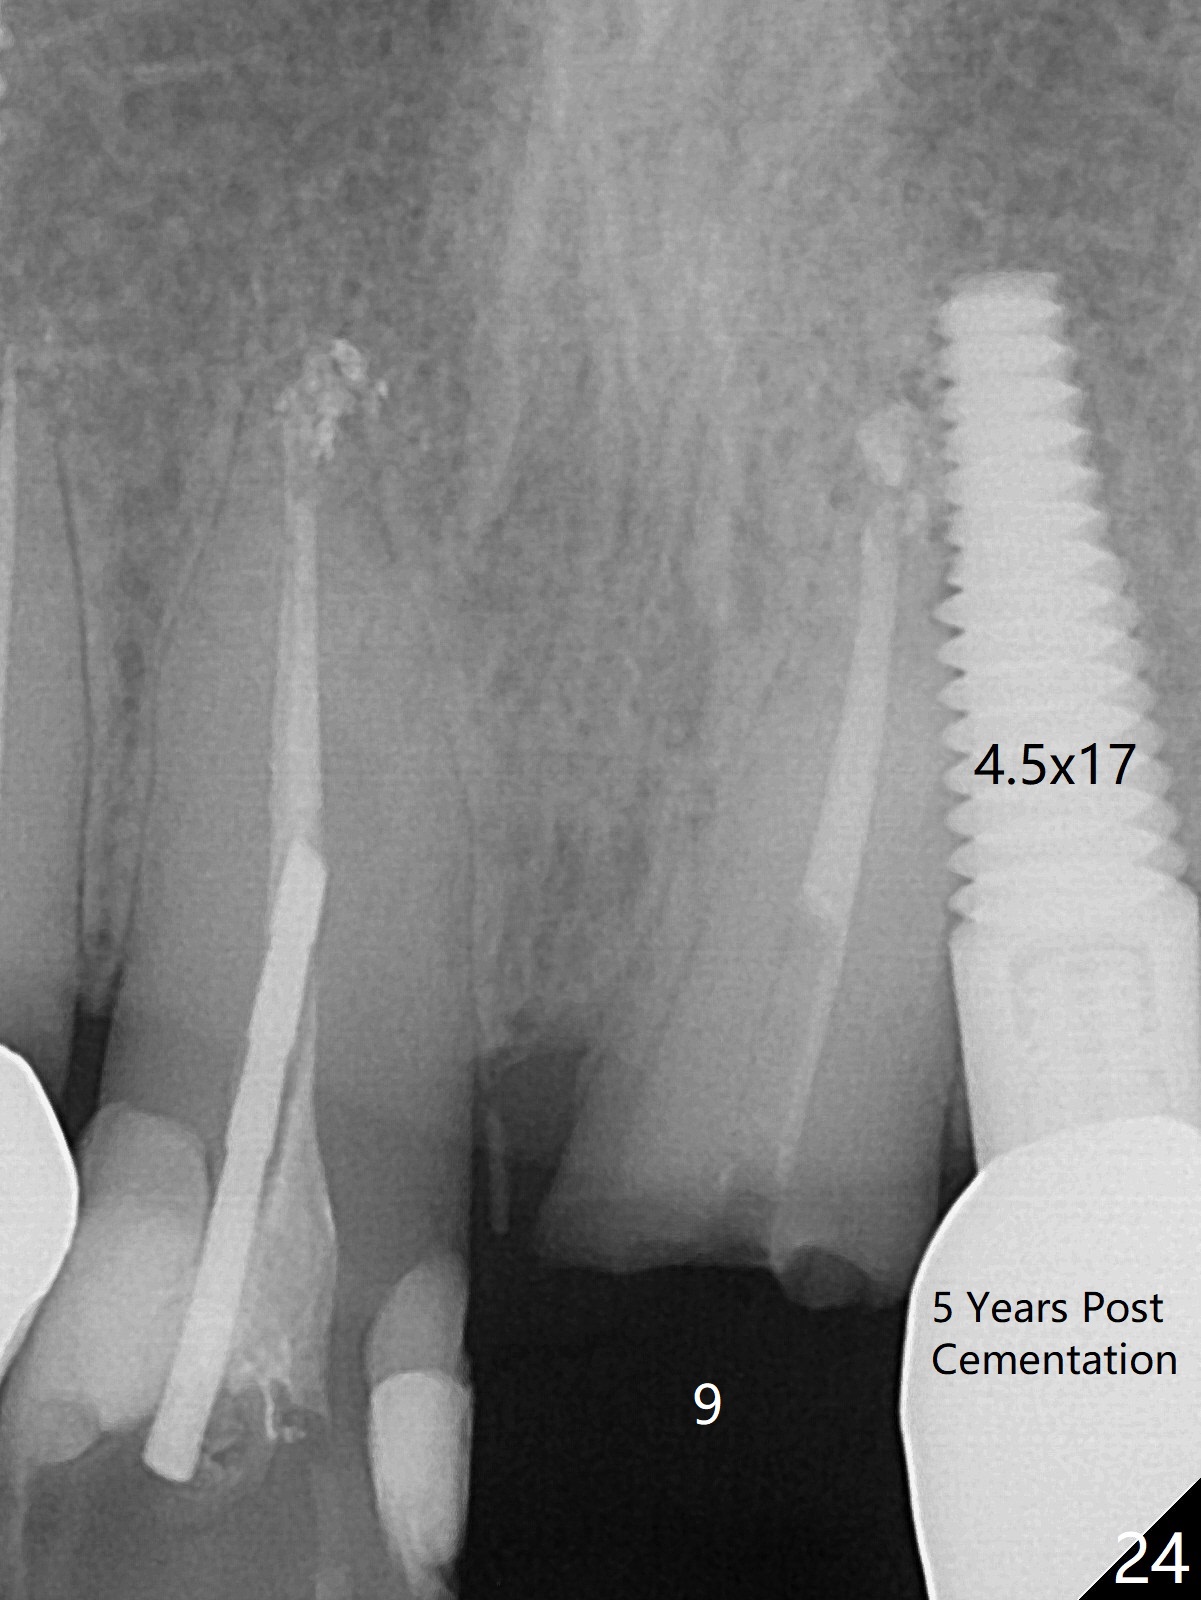

Six months post cementation, the tooth #9 becomes symptomatic.  Is it possible that the implant at #10 is too close to the root of #9?  It is asymptomatic after pulpotomy, but the tooth fractures equi/supragingivally.  Two PAs taken while RCT show osteointegration at #10-12 (Fig.18,19).  While the bone density increases at #10 regular implant, there is minimal bone loss around the 1-piece implants 13 months post cementation (18 months postop, Fig.20,21).  The gingiva remains healthy 19 months post cementation (Fig.22).  76岁病人突然打电话说一个植牙牙冠松动,其实9号牙(自然牙)折裂,6,10-13号牙植牙好像没有骨质吸收(图二十三至二十五),10-13牙位牙龈健康(图二十六,行使功能五年)。9号牙牙冠重新粘固后,显示前牙深覆合,深覆盖(图二十七,二十八)。如果再次脱落需要植牙,选择一段式有助于植入和修复,因为植体和基台直径小。两段式植牙相对基台直径至少4,或者4.5毫米,前牙修复显得笨重。由于9,10牙根和植体接近,9号牙植体需要偏小而长,3x14或者15毫米(图二十九)。